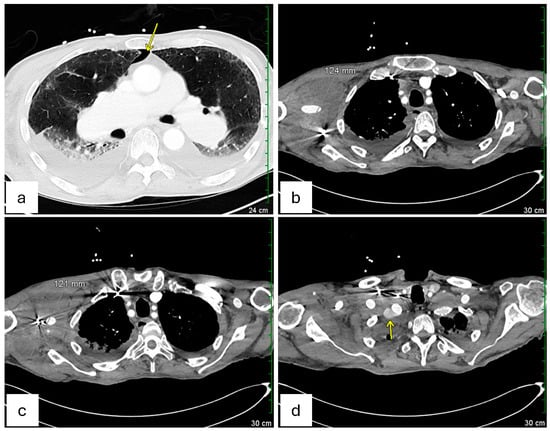

Doppler ultrasound of the right upper extremity confirmed an occlusive deep vein thrombosis of the right axillary vein and a concurrent occlusive superficial thrombosis in the basilic vein (Figure 1a,b). There was also the suggestion of a perivascular hematoma in the region of his subclavian artery stent (Figure 1e,f). Concerned about a possible arterial origin for the hematoma, Vascular Surgery was consulted. A subsequent CT angiogram of the right extremities identified contained ruptures in the right subclavian arteries near the existing stent-grafts, explaining his acute upper extremity swelling and pain (Figure 2a,b). Baseline serum creatinine on admission was approximately 0.84 mg/dL and remained stable (0.71 mg/dL the next day) after this contrast-enhanced imaging, indicating preserved renal function post-CTA (Table 1).

Figure 1. Doppler ultrasound of right arm venous system. (a,b) Occlusive thrombosis of the right axillary vein and right basilic vein is shown by the lack of the Doppler signal compared with other patent veins. (c,d) Examples of patent veins that showed Doppler signal, including the proximal (c) and distal (d) part of the subclavian vein. (e,f) Possibly questionable hematoma in the region of the right subclavian stent as pointed by the yellow arrow.